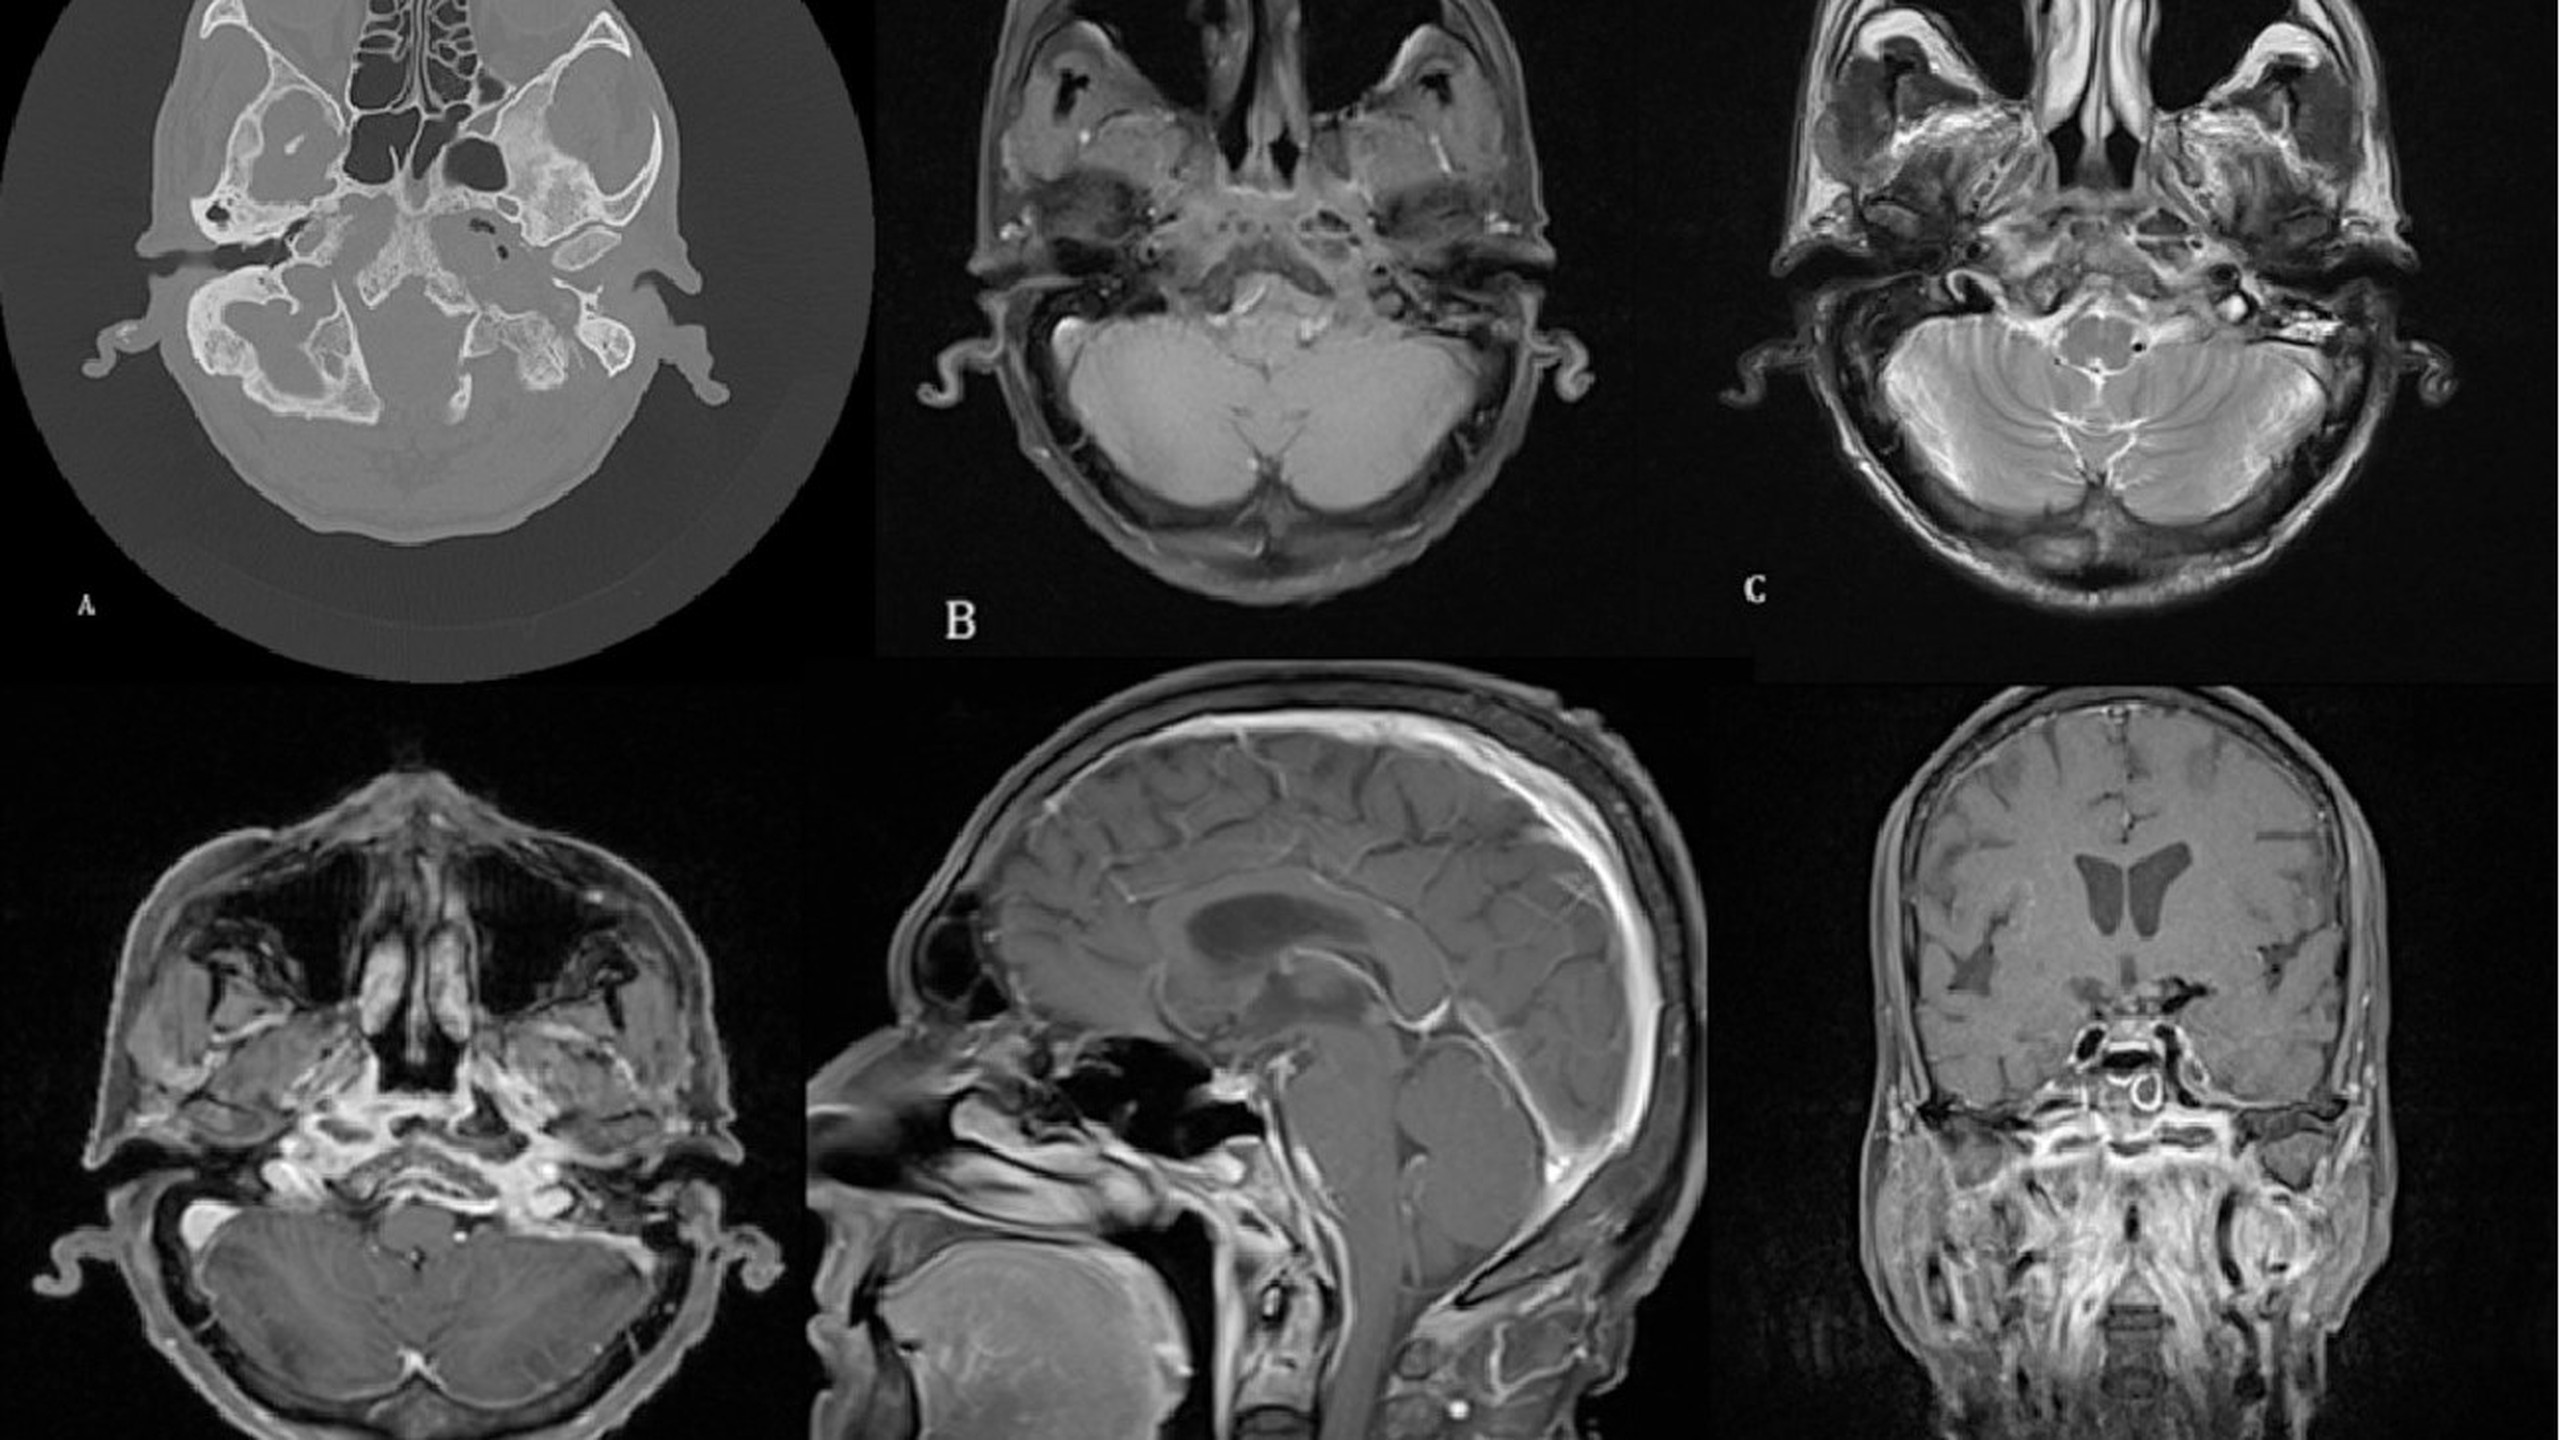

Viêm xương sọ là một tình trạng tương đối hiếm gặp, thường xảy ra như một biến chứng của nhiễm trùng tai hoặc xoang tiến triển ở những bệnh nhân đái tháo đường hoặc bị suy giảm miễn dịch. Chẩn đoán viêm xương sọ bằng lâm sàng và cận lâm sàng, tuy nhiên bệnh thường được chẩn đoán muộn. Thuốc kháng sinh dài hạn kết hợp với phẫu thuật cắt bỏ mô trong các trường hợp nặng là phương pháp điều trị chính. Viêm xương sọ là tình trạng nguy hiểm đến tính mạng nếu không được chẩn đoán và điều trị sớm.

Viêm xương sọ hay còn gọi là viêm tủy xương nền sọ (SBO) là một căn bệnh nguy hiểm có nguy cơ biến chứng cao như nhiễm trùng thần kinh. Thông thường, tình trạng viêm xương sọ là do nhiễm trùng từ các mô lân cận như là biến chứng của nhiễm trùng tai, huyết khối xoang tĩnh mạch, viêm màng não, áp xe, bệnh lý thần kinh sọ não và xâm lấn động mạch cảnh. Viêm xương sọ cũng có thể bắt nguồn từ nhiễm trùng cạnh mũi, chẳng hạn như viêm xoang bướm hoặc xoang sàng mà không liên quan đến viêm tai ngoài.

Nhiễm trùng là nguyên nhân gây ra viêm xương sọ, nhiễm trùng có thể là do vi khuẩn hoặc nấm. Bệnh nhân mắc viêm xương sọ do vi khuẩn có nhiều khả năng bị viêm tai ngoài, viêm tai giữa hoặc viêm xương chũm, dẫn đến điếc, đau tai và chảy mủ ở tai. Những bệnh nhân bị ức chế miễn dịch và viêm xoang mãn tính, đau xoang, sưng mặt hoặc quanh hốc mắt và chảy nước mũi thường xuyên, có khả năng mắc viêm xương sọ do nấm nhiều hơn.

Nhiễm trùng gây viêm xương sọ xâm nhập vào tai và nền sọ qua ống tai ngoài. Điều này thường xảy ra ở điểm nối giữa phần sụn và phần xương của ống tai ngoài. Chấn thương ở điểm nối này tạo điều kiện cho nhiễm trùng xâm nhập vào các mô bên dưới khiến bệnh lây lan nhanh chóng và sau đó xâm nhập đến xương nền sọ. Viêm tủy xương nền sọ cũng có thể xảy ra sau nhiễm trùng tai giữa.